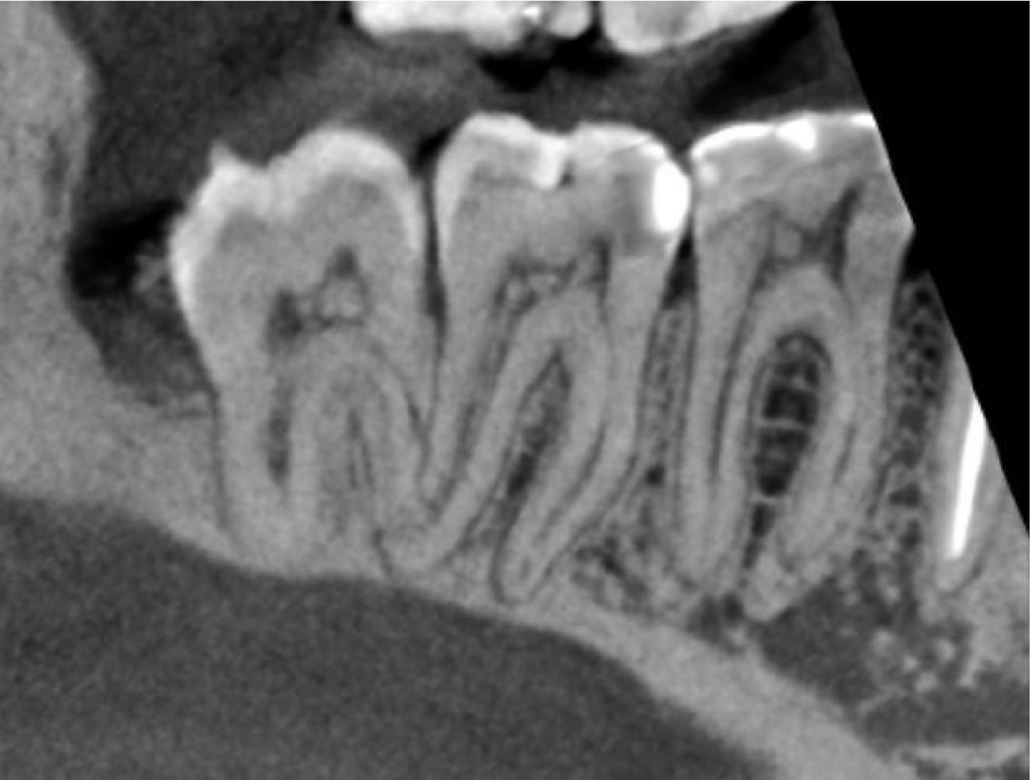

Cropped panoramic of LR6-8 and cross section of alveolar ridge of LR6 region showing patent root canals, normal periodontal ligament width and lamina dura. Also seen is the enlarged follicle space associated with the LR8.

Cropped panoramic of LR6-8 showing pulp stones in the LR6, LR7 and LR8.

The LR6-8 have pulp stones.